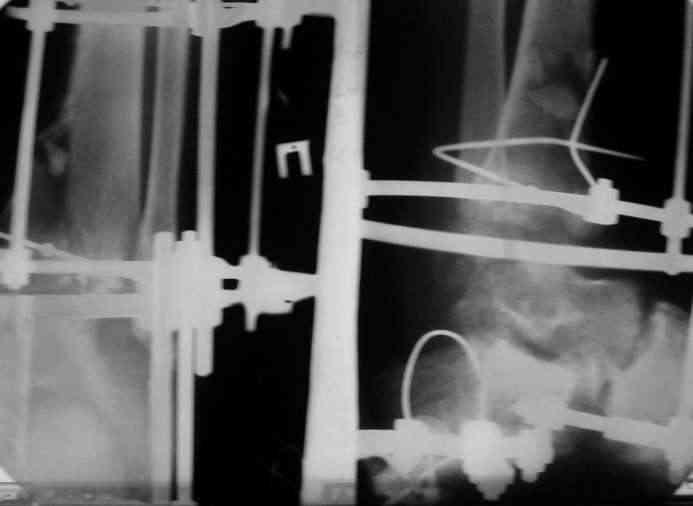

Вчера (прошло около 8 месяцев)больной обратился ко мне в очередной раз с жалобами на боли умеренно-жгучего характера в области выстояния концов болта-стяжки. На момент осмотра:укорочение левой нижней конечности на 1,5 см; гипотрофия медиальной группы мышц голени и четырехглавой мышцы бедра; передвигается без дополнительной опоры в ортопедической обуви на растояние до 5 км; работает приемщиком цветных металлов (приходится перетаскивать грузы). Нарентгенограмме, насколько это можно видеть, костного блока сформировать не удалось, но движений в голеностопном суставе нет - ни активных, ни пассивных. Послеоперационные рубцы б/о; свищей и нагноения не было. Активно больногонаблюдать не приходилось, т.к. проживает в другом городе.

Стоит ли необходимость удаления болта-стяжки из-за болевого синдрома?

Уважаемый Никита! На мой взгляд болт-стяжку

придется удалить.Как правило,если уж пошла миграция металла,то либо ломается, либо нагнаивается. После удаления болта может появиться подвижность в суставе-при несостоятельности артродеза-и усиление болей.

В этом случае возможно предпринять корригирующую остеотомию большеберцовой- выше места перелома и повторно артродез в аппарате. Необходим тщательный контроль больного- спицевые нагноения чаще всего у недисциплинированных, плохо контролируемых пациентов.